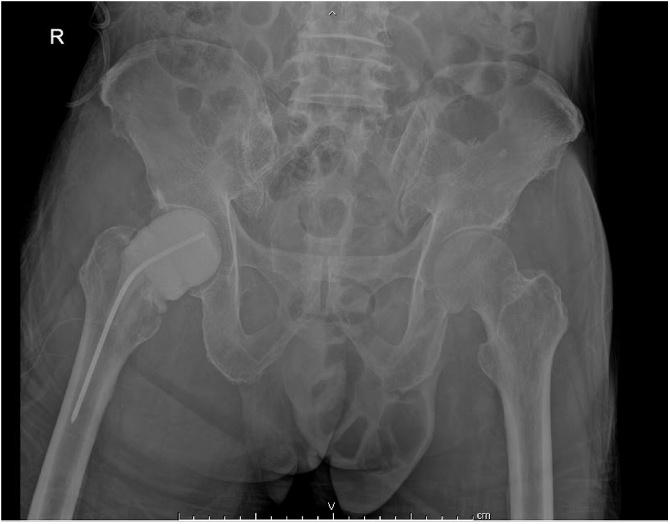

A 75-year-old male had right hip pain for two weeks after falling on his right hip. The patient was diagnosed as pathological fracture with hematologic malignancy. He was scheduled for bipolar hemiarthroplasty. However, an intraoperative finding found that the hip joint was filled with pus. The treatment was successful with a two-stage procedure. The first stage was implantation of an antibiotic cement spacer and the second stage was total hip replacement.

一名75岁男性在右髋部摔倒后右髋部疼痛两周。该患者被诊断为血液系统恶性肿瘤导致的病理性骨折。他计划接受双极半髋关节置换术。然而,术中发现髋关节充满脓液。通过两阶段手术治疗成功。第一阶段是植入抗生素骨水泥间隔物,第二阶段是全髋关节置换。

股骨颈骨折后感染性关节炎是一种在诊断和治疗上需要特别关注的并发症。等待手术的患者髋部疼痛加剧或出现感染迹象可能提示髋关节感染。在这种情况下,两阶段手术是首选的治疗方法。